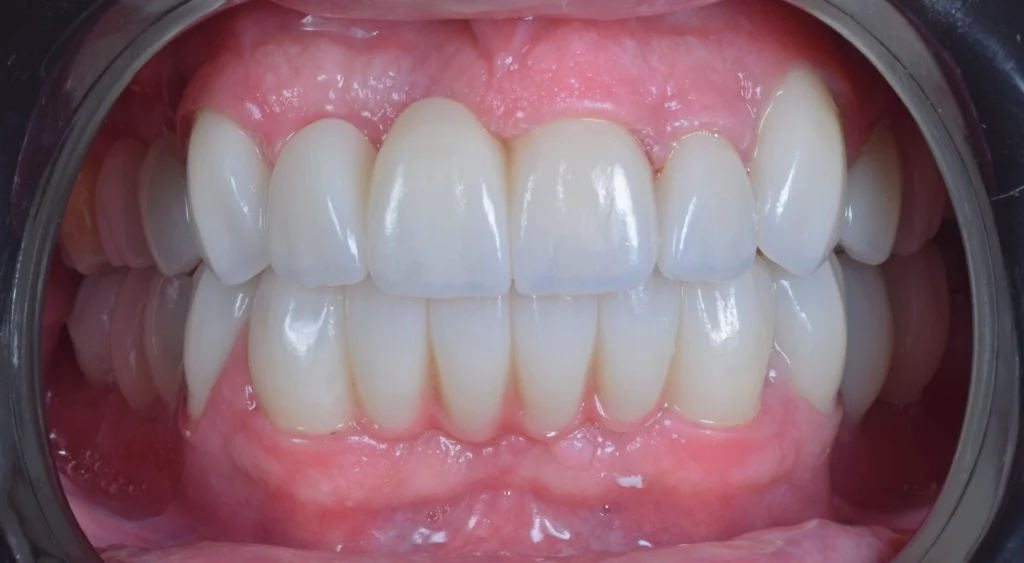

The final result was achieved using high-quality monolithic zirconia restorations—delivering a strong, natural-looking, and long-lasting smile.

The transformation speaks for itself. Today, the patient is shining, happy, and full of confidence. His fear has been replaced with trust, and his smile reflects a completely new chapter in his life.